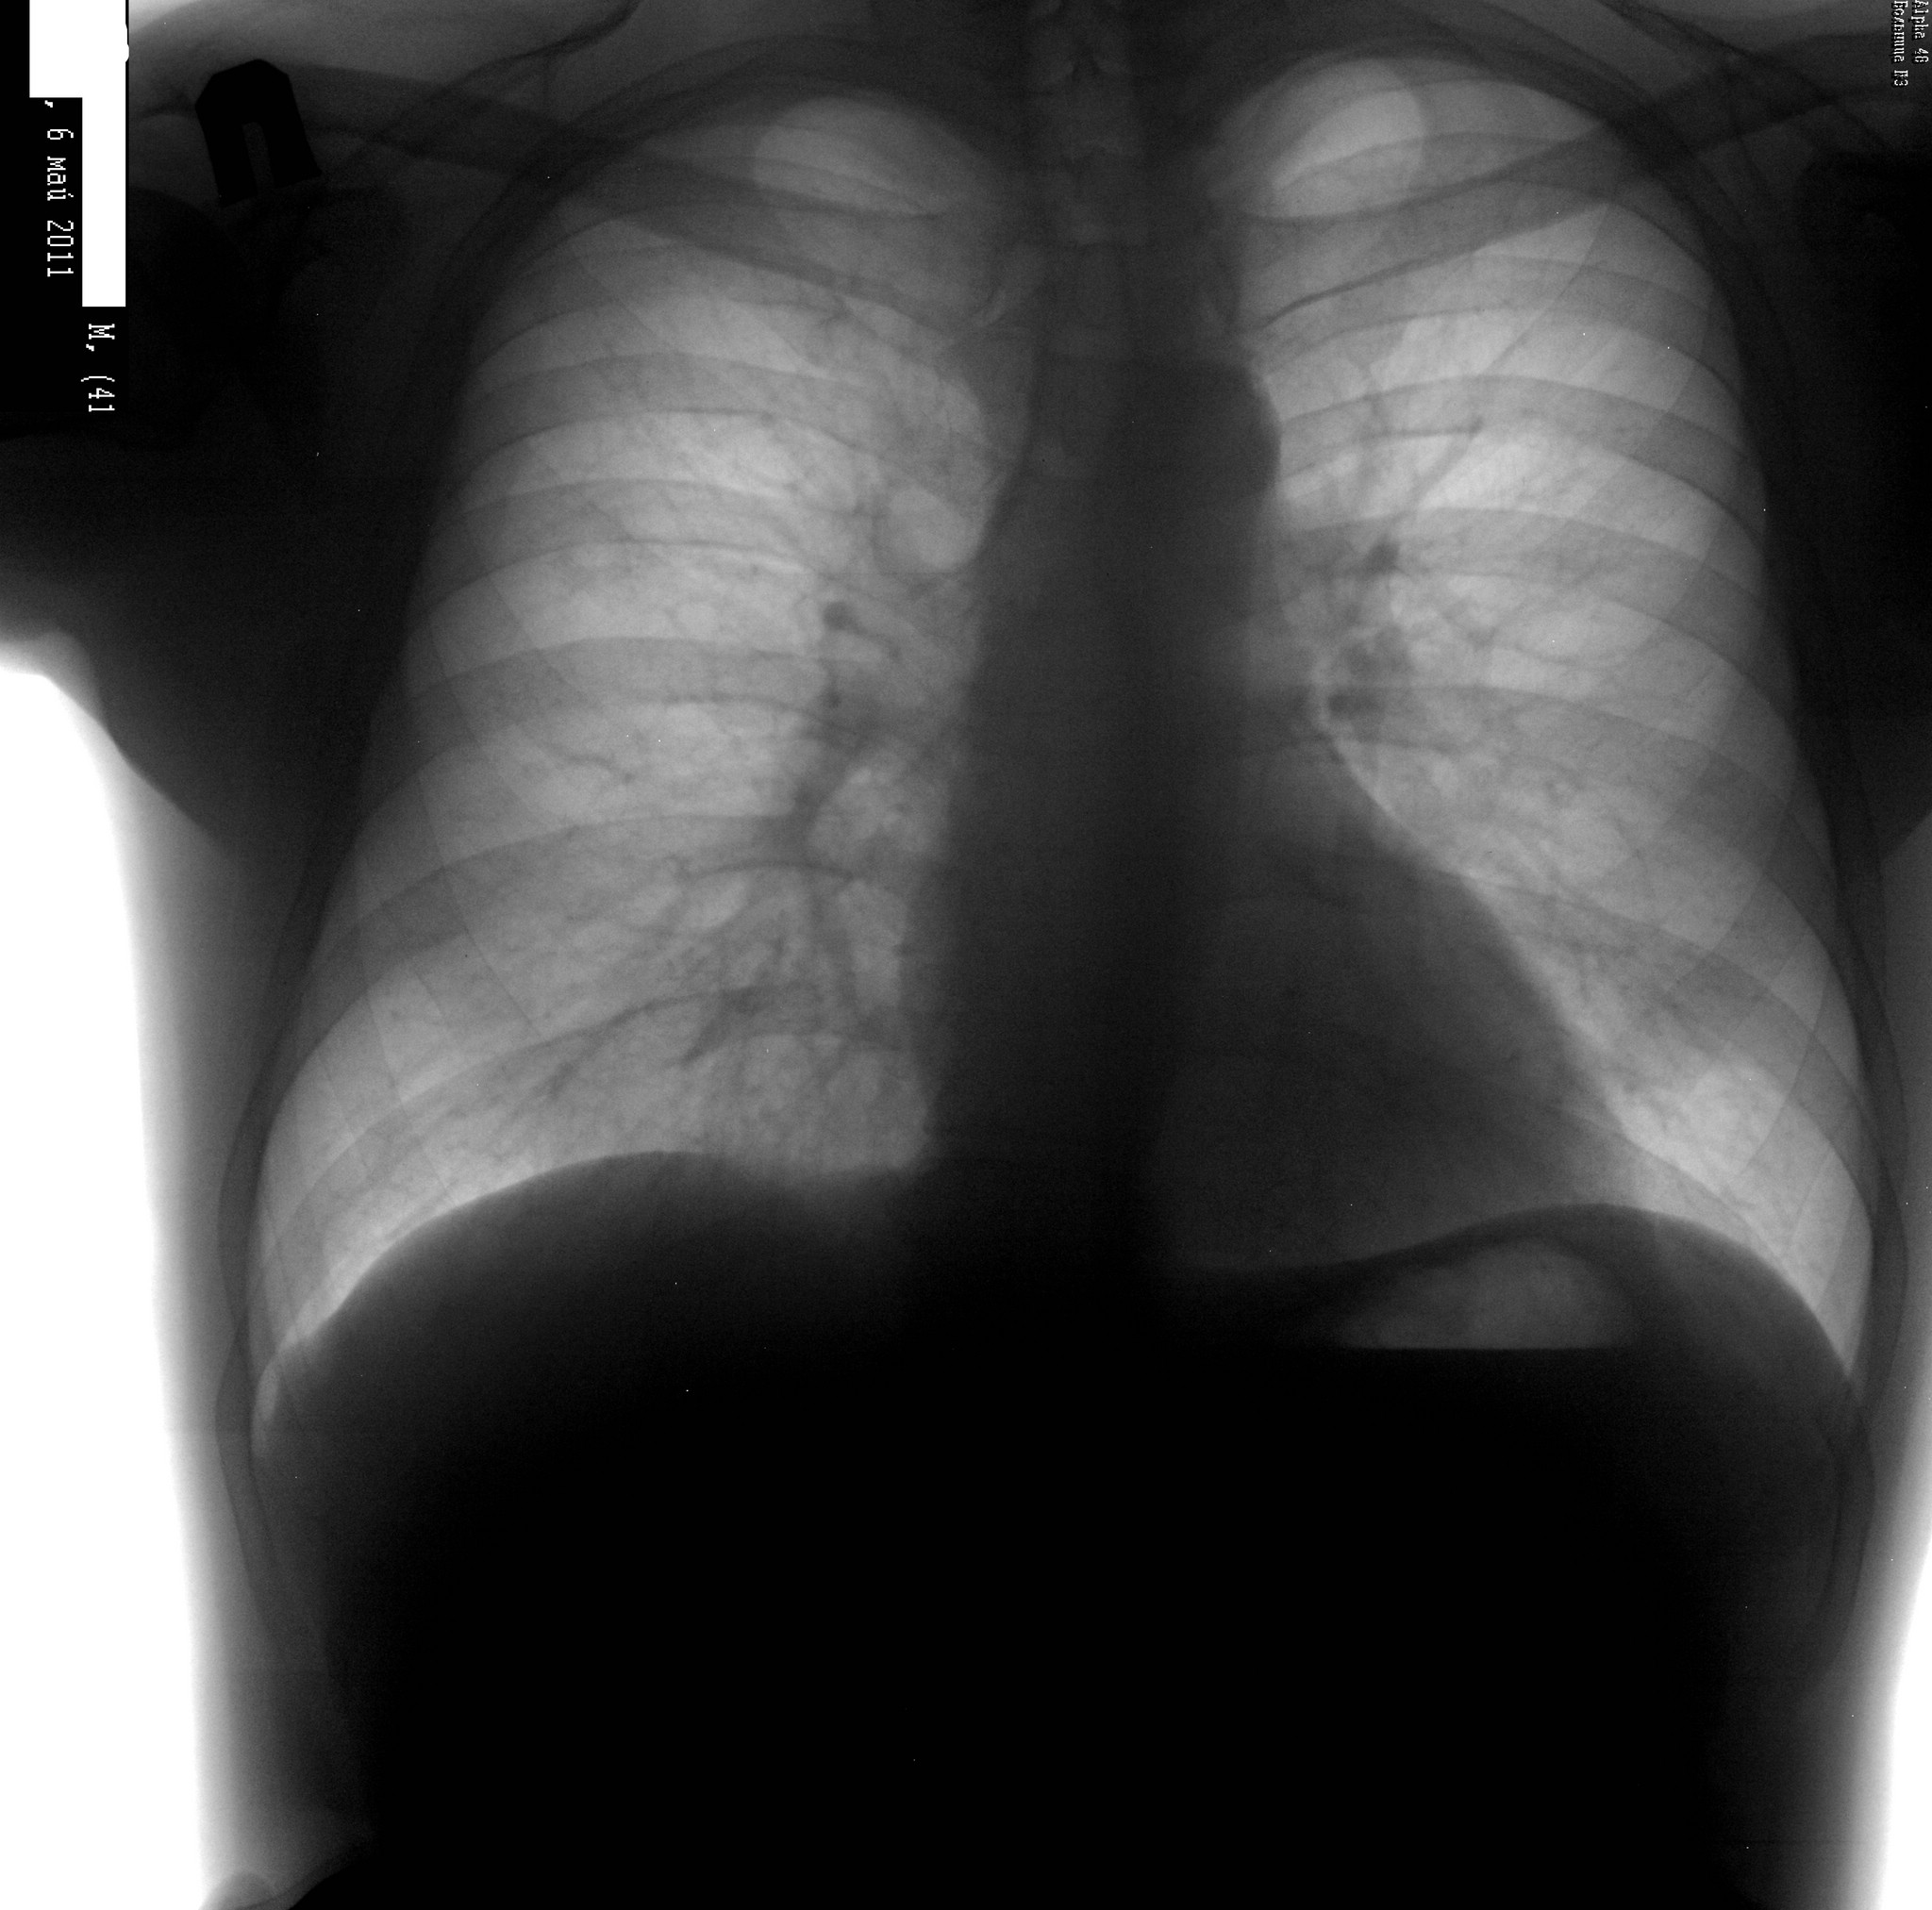

Выставлено в качестве самоконтроля (написал, но сомневаюсь в заключении). Мужчина, 41. контроль после правосторонней н/д пневмонии. Первого снимка нет, делали не у нас. Вас что-то смущает?

Спасибо)) Написал в заключении дренированная полость? и поствоспалительная плевродиафрагмальная спайка в правом реберно-диафрагмальном синусе. На боку тоже не нашел.

Маленькая полость справа в проекции переднего отрезка 3-го ребра. На боковой я ее не нашла.

По-моему, это вообще "тень на плетень"... Я бы на скопии вдох-выдох сделала. То, что никакого тбс там нет - это точно (работаю в туб дисп - насмотрелась) - каверн на фоне неизмененной легочной ткани не бывает, даже таких мелких. Окружающая легочная ткань абсолютно интактна. Полостюшка, конечно же, рисуется, но большой вопрос, есть ли она. Задние снимки очень помогают, не стоит пренебрегать.